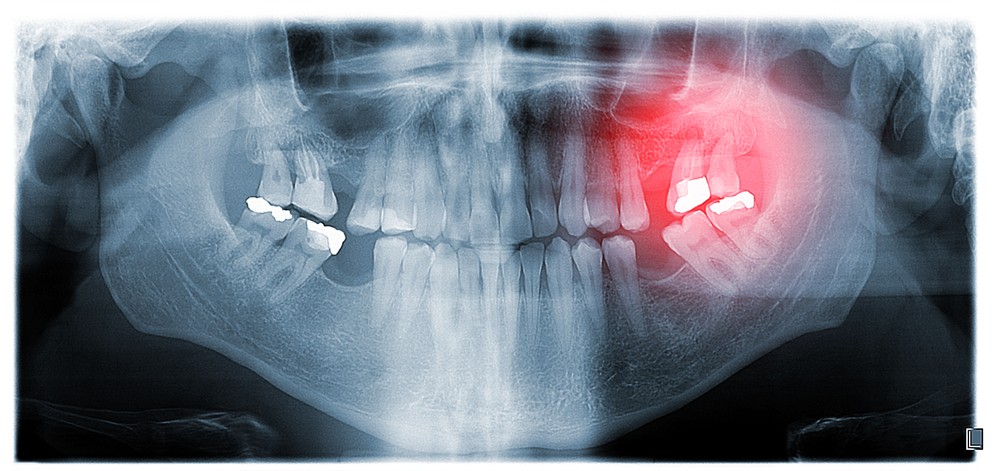

Parodontoza este o boală cronică ce afectează țesuturile de susținere ale dinților, cum ar fi gingiile și osul alveolar. Procesul inflamator declanșat de prezența bacteriilor la nivelul gingiilor produce substanțe toxice ce degradează treptat aceste țesuturi. În absența unui tratament adecvat, acest proces poate avansa, ducând la formarea de buzunare parodontale, retracția gingiilor și, în final, la pierderea dinților.